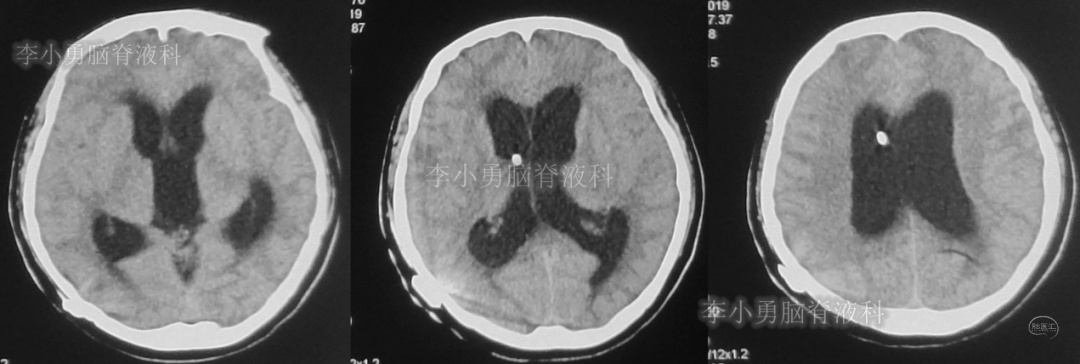

此后1个多月(2019年11月4日到2019年12月16日),患者意识一直无改善,一直呈模糊状态,多次复查头颅CT(图-12至图-20)见脑室大小反复变化不定,医生根据CT结果等反复多次调节分流泵压力(具体过程家属回忆不起)。但患者病情无好转却逐渐加重,逐渐不能咀嚼、吞咽及进食,卧床不起。

图-12:2019年11月8日头颅CT

图-13:2019年11月16日头颅CT

图-14:2019年11月19日头颅CT

图-15:2019年12月3日头颅CT

图-16:2019年12月10日头颅CT

图-17:2019年12月12日头颅CT

图-18:2019年12月13日头颅CT

图-19:2019年12月14日头颅CT

图-20:2019年12月16日头颅CT